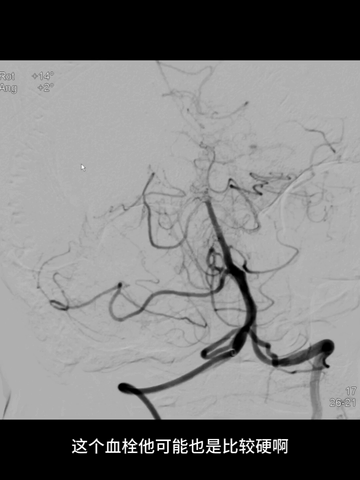

经微导管送入一4*20mm取栓支架(S AB),释放支架后造影示闭塞再通,支架头端恰好位于基底动脉远端。

考虑到双胚胎后交通,基底动脉管径一般比较小,故回收取栓支架时6F中间管只是行至基底动脉近端,未敢深入其中。

取栓后造影示:基底动脉再通,如之前预判,其管径确实细小;同时造影剂逆流至左椎动脉V4段,显示其管径明显纤细。

2、以轻型卒中起病的基底动脉栓塞本就少见,而在短时间继而进展加重的基底动脉栓塞就更是罕见。虽最终未能查明栓塞来源,猜测可能的原因为:血栓进入椎基底动脉,由于血栓质地较硬,加之基底动脉自身管径较小,故此硬质血栓卡顿于基底动脉近端,因侧枝循环部分代偿基底动脉中远段血流,或硬质血栓未完全阻断血流,故发病初期症状轻;后因侧枝衰竭,或血栓因血流持续冲击变形迁移而完全阻断血流,缺血程度加重,进而症状进展。